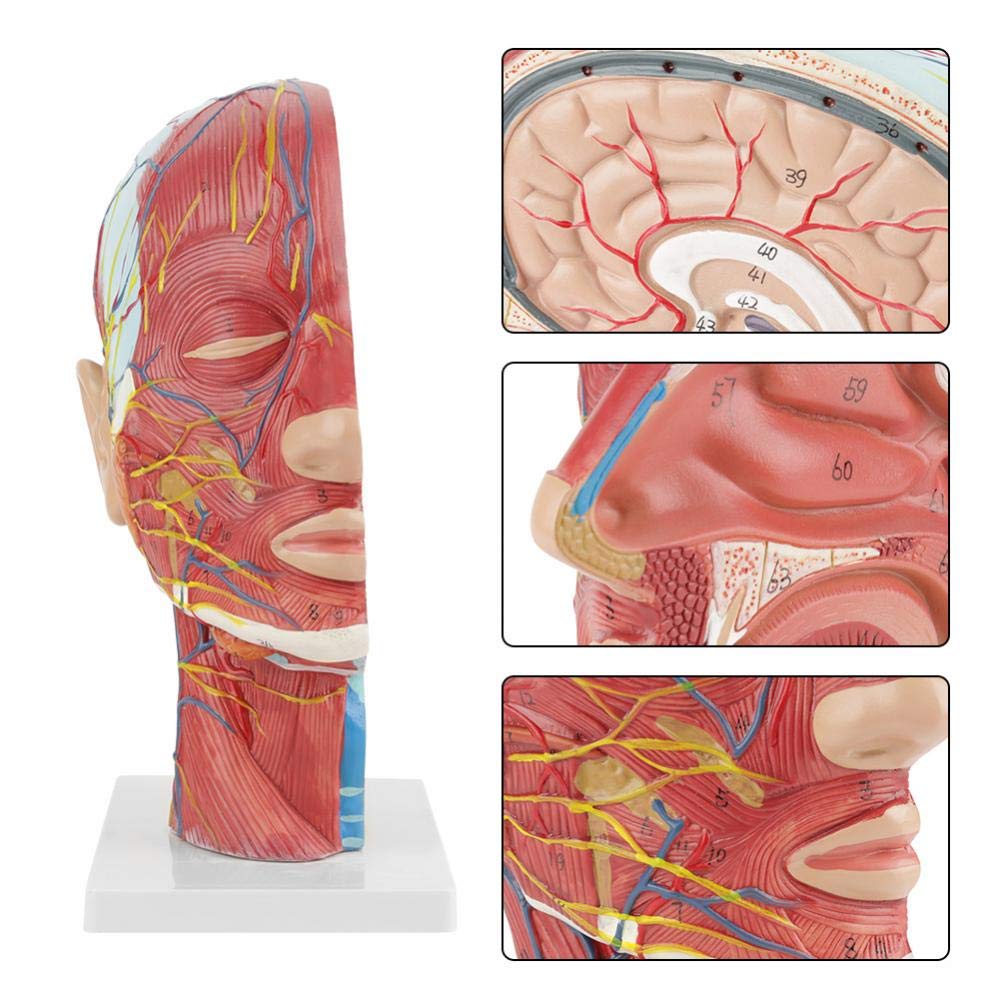

| Ciri -ciri | Model ini menunjukkan morfologi tempatan bahagian dalam dan luar bahagian median sagittal kepala dan leher, serta struktur saluran darah dan saraf, dan terdapat 84 bahagian yang menunjukkan tanda -tanda secara keseluruhan. |

【1: 1 LifeSize】 Seksyen Median 1: 1 Model otot vaskular neural yang besar dan leher besar (sebelah kanan). Pengerjaan yang baik. Menawarkan pelbagai ciri anatomi.

【Model otot neurovaskular cetek】 Sangat terperinci, nombor yang ditandai, telinga boleh dilepaskan, memperdalam pemahaman otot, kapal, saraf dan struktur dalaman kepala & leher. Red-artery, biru-vein, kuning-saraf.

【Ciri -ciri】 Ia menunjukkan otot -otot cetek muka yang terdedah; saluran darah cetek & saraf muka & kulit kepala; struktur dalaman kelenjar parotid & saluran pernafasan atas; Struktur keratan rentas sagittal tulang belakang serviks.

Model ini menunjukkan butiran leher kepala kanan dan bahagian pertengahan sagittal manusia. termasuk cetek

otot muka yang terdedah; saluran darah dangkal dan saraf muka dan kulit kepala; struktur dalaman

kelenjar parotid dan saluran pernafasan atas; Struktur keratan rentas sagittal tulang belakang serviks.

Model ini menunjukkan morfologi tempatan bahagian sagittal medial dan lateral kepala dan leher dan struktur vaskular dan sarafnya, dengan jumlah 100 petunjuk tapak.

Model ini adalah model otot neurovaskular yang besar dan leher yang besar, 1 komponen, menunjukkan butiran kepala kanan dan leher manusia dan bahagian sagittal median, termasuk otot -otot dangkal yang terdedah pada muka, kapal cetek muka dan skalp, saraf, saraf, saraf, saraf, saraf, saraf, saraf, saraf, saraf, saraf, saraf, saraf, saraf, saraf, saraf, saraf, saraf, saraf, saraf, saraf, saraf, saraf, saraf, saraf, saraf, saraf, saraf, saraf, saraf, saraf, saraf, saraf, saraf, saraf, saraf, dan struktur medial kelenjar parotid dan saluran pernafasan atas, dan struktur bahagian sagittal tulang belakang serviks